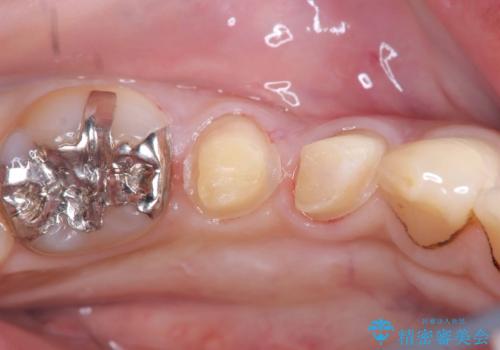

- CRが劣化し欠けてしまっている状態でした。 虫歯を除去後、歯を破折から守るためオールセラミッククラウンで治療を行いました。

CRが欠けてしまっていて食べ物が凄く詰まる状態でした。